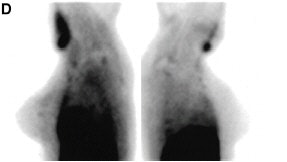

| Images taken with a conventional gamma camera (D) showed possible minimal radiotracer uptake in superior left breast. Biopsy revealed a 4-mm infiltrating ductal carcinoma. Images and captions republished with permission of the Society of Nuclear Medicine from Brem et al, July 2002, Vol. 43:7, pp. 909-915. |

Detection of unsuspected cancer with high-resolution breast-specific gamma camera in 33-year-old woman, 2 years after lumpectomy and radiation therapy for infiltrating ductal carcinoma of the right breast. Mediolateral oblique and craniocaudal mammograms (A and B) of the left breast show normal findings.